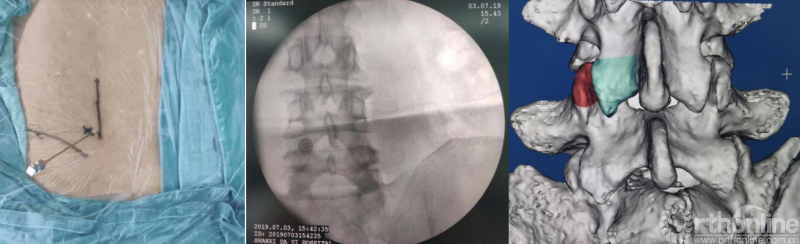

第一步“定”:X线定位在上位椎体下关节突下三分之一部;

第二步“辨”:镜下辨别下关节突关节囊;

第三步“凿”:凿除部分下关节突,显露上关节突及黄韧带;

第四步“分”:分离上关节突及黄韧带;

第五步“咬”:咬除部分上关节突,显露椎间盘及神经根;